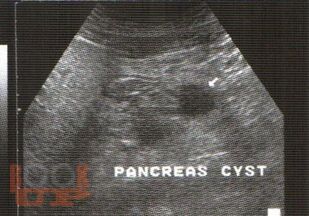

В практическом руководстве отражены вопросы ультразвуковой диагностики доброкачественных, злокачественных опухолей печени, поджелудочной железы, метастатического поражения печени, пороков развития, заболеваний гепатопанкреатодуоденальной зоны. Практическое руководство предназначено для специалистов лучевой диагностики, хирургов, онкохирургов.